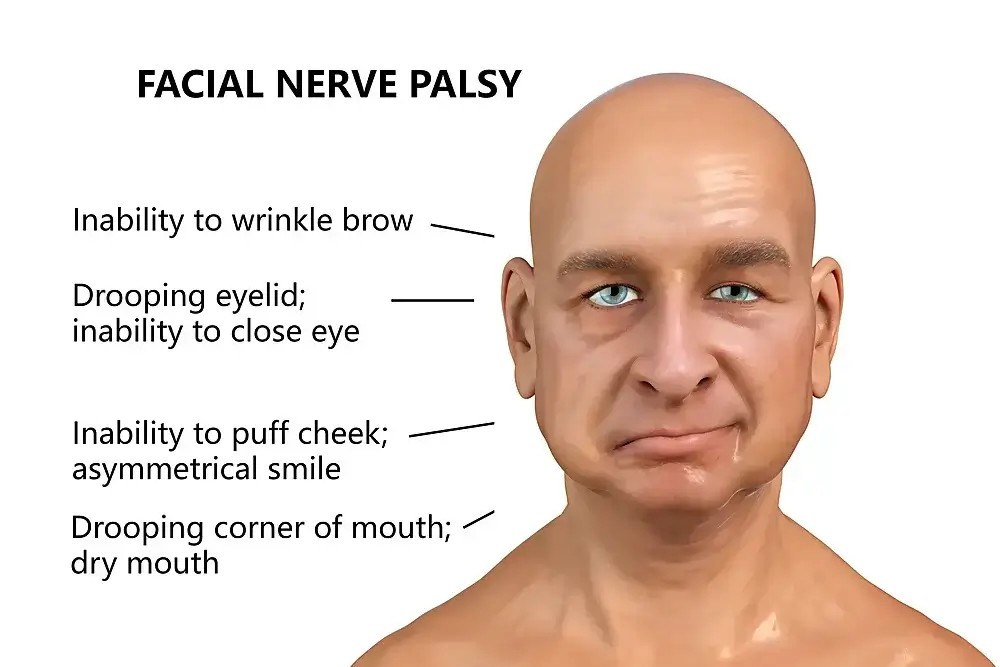

Bell’s Palsy (Facial Nerve Paralysis)

There are more than 100 different types of facial nerve paralysis; Bell’s palsy is one of them. Bell’s palsy is a condition of the face that can cause paralysis on one side of the face. It is named after Canadian doctor James Bell, who first described it in 1876.

Bell’s palsy affects people of all ages, but is most common in adults over 40. The cause is unknown, but it is believed to be caused by a virus. Symptoms include paralysis of the facial muscles, drooping eyelids, and difficulty speaking. Bell’s palsy is a debilitating disorder of the facial muscles. It can lead to difficulty with speech, eating, and breathing.